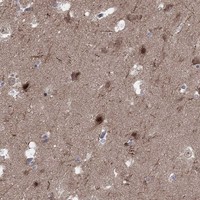

Immunohistochemical staining of human hippocampus shows strong nuclear positivity in neuronal cells.